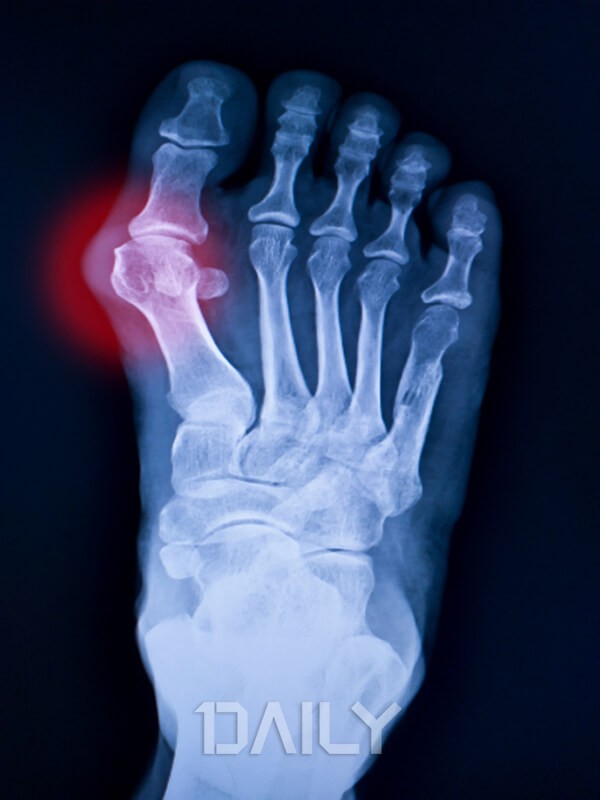

ÁÖ·Î ¾öÁö¹ß°¡¶ô ±ÙÀúºÎ °üÀý¿¡¼ ÅëÁõÀÌ ºÎ±â³ª ¿°¨°ú ÇÔ²² ¹ß»ýÇÑ´Ù. ÆÈ²ÞÄ¡, ¹«¸, ¹ß¸ñ, ¼Õ°¡¶ô µîÀÇ ¾î´À ºÎÀ§ °üÀýÀ̵ç Áõ»óÀÌ ³ªÅ¸³¯ ¼ö ÀÖ´Ù. º¸ÅëÀº ¹ã°ú »õº® »çÀÌ¿¡ ÅëÁõÀÌ ½ÉÇÏ°Ô ÀϾÙ. ÅëdzÀ» Ä¡À¯ÇÏÁö ¾Ê°í ¹æÄ¡ÇÏ¸é °üÀý ÁÖÀ§¿¡ ´Ü´ÜÇÑ ¸Û¿ïÀÎ ¡®Åëdz °áÀý¡¯ÀÌ »ý°Ü³ª ¹ß°¡¶ôÀÌ ±Á°Å³ª ±â´ÉÀå¾Ö¸¦ ÀÏÀ¸Å°±âµµ ÇÑ´Ù. ±ÓºÒ¿¡ ÇÏ¾á ½Ò¾Ë °°Àº ¹ÝÁ¡ÀÌ ³ªÅ¸³ª±âµµ ÇÑ´Ù.

ÅëdzÀÇ Áõ»óÀ» È£¼ÒÇÒ °æ¿ì, Àǻ簡 ÁøÂûÀ» ÅëÇØ È®ÀÎÇÒ ¼ö ÀÖÀ¸¸ç ÀÌÈÄ Çǰ˻糪 °üÀý¾×À» »Ì¾Æ Çö¹Ì°æÀ¸·Î °üÂûÇÏ´Â µîÀÇ ¹æ¹ýÀ¸·Î Áø´ÜÇÒ ¼ö ÀÖ´Ù. º¸Á¶ÀûÀ¸·Î X-ray³ª dual-energy CT ÃÔ¿µÀ» Çϱ⵵ ÇÑ´Ù.